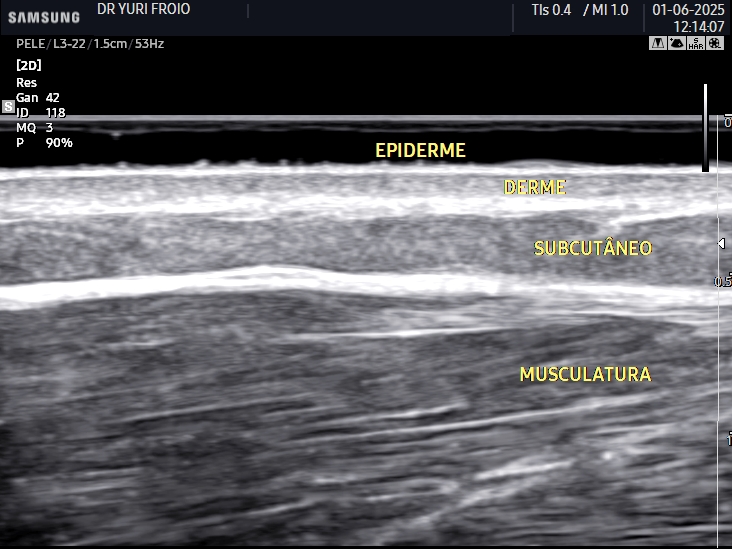

O ultrassom dermatológico é uma ferramenta avançada para avaliação da pele e tecidos subcutâneos. Permite analisar lesões, medir a espessura da pele e auxiliar no diagnóstico de tumores, cistos e inflamações. É um exame seguro, sem radiação e com alta precisão diagnóstica.